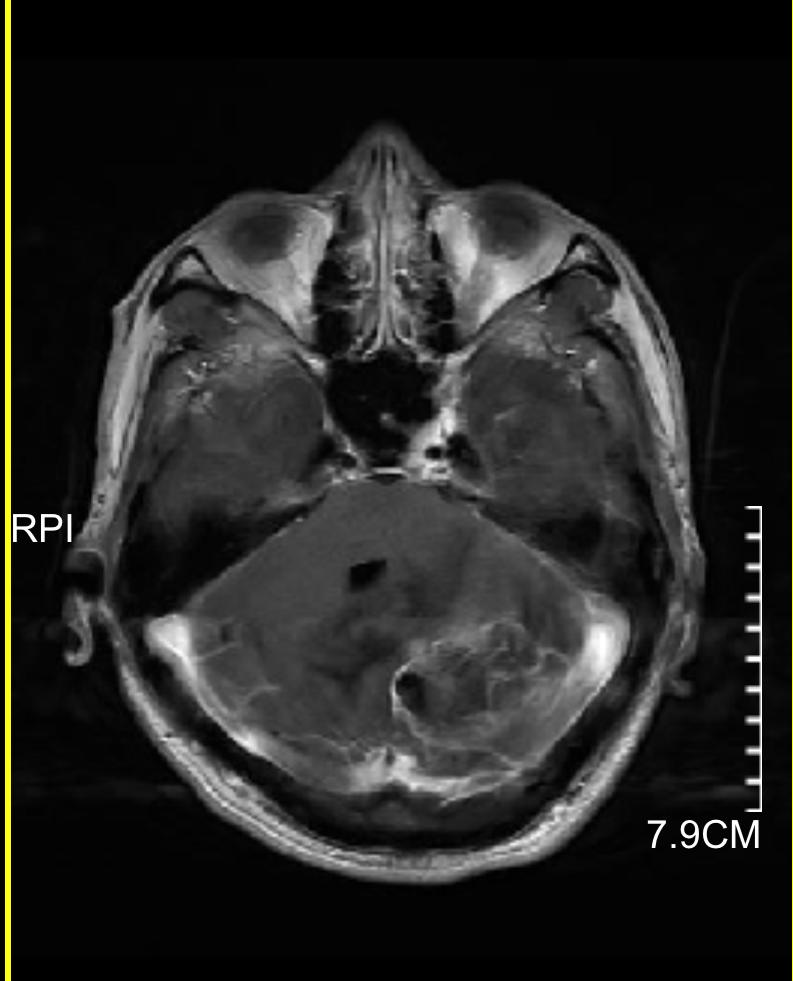

下图的病例是一个以头痛、行走不稳为主要表现,查头颅磁共振发现颅内三个大的转移灶,同时肺部发现巨大肿瘤,脑内病灶给予全部切除,术后根据基因检测结果进行化疗及靶向、免疫治疗。

小脑巨大转移瘤

小脑转移瘤已切除